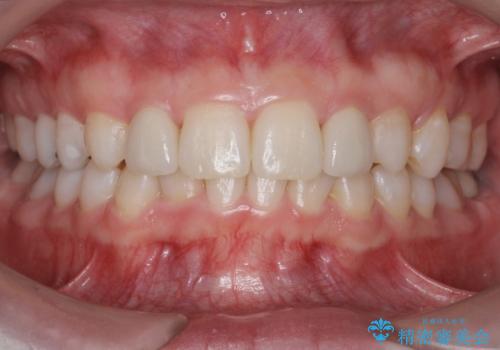

抜歯したスペースを使い、歯並びを整え、さらにその隙間を利用して細い歯を大きく整えてセラミックで被せるという総合的な治療を行いました。

マウスピース矯正→上顎両側2番のセラミック、左下67の虫歯治療 の順で行いました。

矯正治療→ホワイトニング→セラミック の順で行なっています。

ホワイトニングで綺麗に白くした歯に合わせて、被せています。